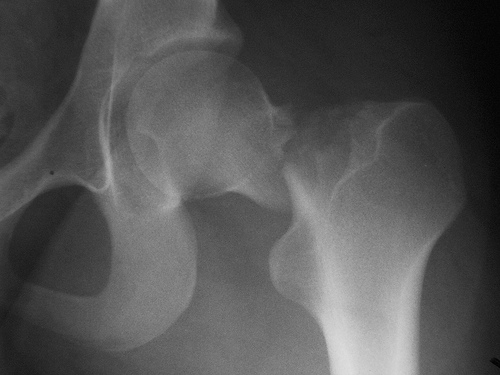

Un estudio encuentra que menos del 10% de los pacientes había iniciado tratamiento para osteoporosis luego de 6 meses de la fractura, a pesar de los beneficios demostrados de los fármacos en esta indicación. JAMA Network Open, 20 de julio de 2018

Se calculó el puntaje FRAX y se realizó densitometría a aquellas con riesgo de fractura elevado, dejando el tratamiento a criterio del médico de cabecera. Se logró una reducción del 28% (IC 11-41%) de las fracturas de cadera. The Lancet, 15 de diciembre de 2017

Benzodiacepinas y fracturas de cadera

El uso de benzodiacepinas se asoció a un aumento del riesgo de fractura de cadera en pacientes con y sin enfermedad de Alzheimer. JAMDA, 12 de noviembre de 2016

Fármacos y fracturas en los ancianos

Un estudio halló que más del 75% de los pacientes fracturados recibían fármacos que aumentan el riesgo de fractura. Además, la mayoría los siguió utilizando después. JAMA Internal Medicine, 22 de agosto de 2016